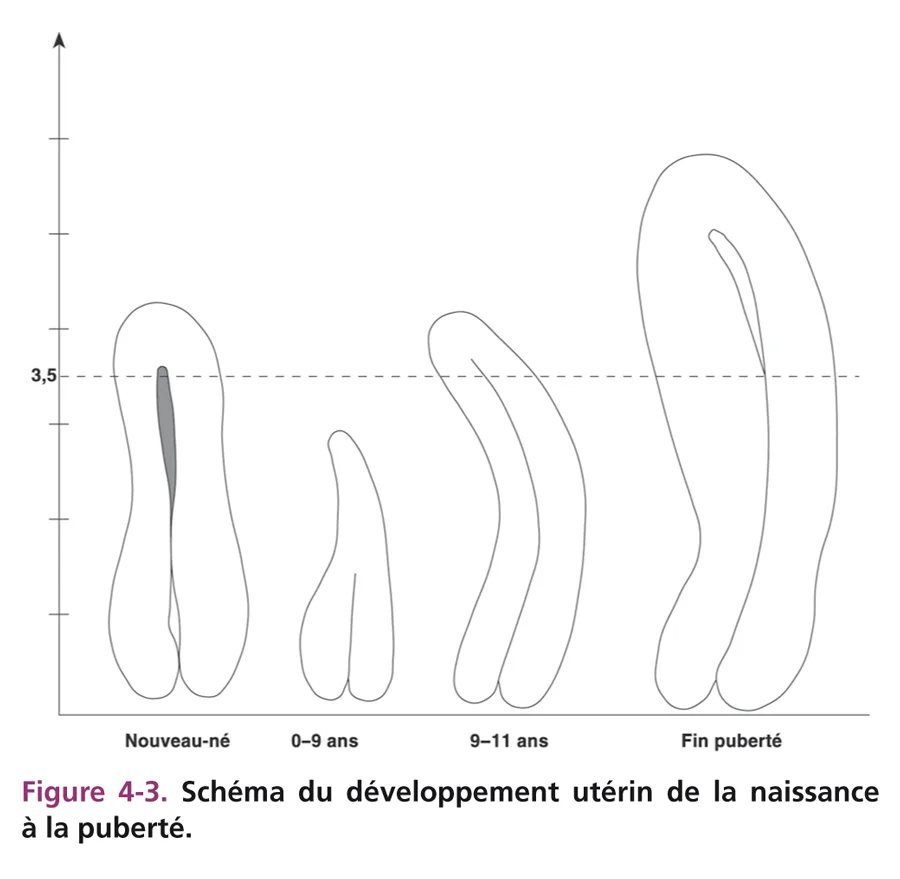

L’utérus des nouveau-nés paraît volumineux du fait de la petite taille du pelvis et de son développement transitoire dû à l’imprégnation normale maternelle pendant la grossesse. Il est épais avec un corps aussi épais que le col, mesuré de 1 à 1,5 cm (fig. 4-1). Sa hauteur est de 3,5 à 4,5 cm. La cavité utérine est soulignée par un écho dense médian, témoin d’un léger développement de l’endomètre. Le vagin sous-jacent présente des parois musculaires hypoéchogènes épaisses, bien visibles. Cet aspect de gros utérus à la période néonatale disparaît en quelques semaines ou mois pour adopter la morphologie impubère normale [1–3]. L’utérus impubère a une morphologie particulière « en goutte » avec un corps utérin fin par rapport au col et à l’isthme plus épais, formant les deux tiers du volume utérin (fig. 4-2A). Le rapport corps sur col est inférieur à 1. La hauteur utérine est mesurée à 3 cm ± 0,5 cm. La taille et l’aspect de l’utérus restent inchangés jusqu’à l’âge de 8 à 9 ans. Son échostructure est hypoéchogène, homogène. La ligne cavitaire n’est pas visible. Un fin écho cavitaire est parfois vu au niveau du col. Les parois vaginales sont fines.

À la puberté (fig. 4-2B), sous l’influence des œstrogènes, l’utérus grossit progressivement et sa croissance s’effectue au niveau du corps qui s’allonge et s’épaissit. L’utérus devient ainsi tubulé puis prend son aspect piriforme pubère. En fin de puberté, il mesure 6 à 6,5 cm de hauteur. La cavité utérine est visible sur toute la hauteur utérine, ce qui témoigne de l’épaississement des parois musculaires, puis de l’épaississement progressif de l’endomètre.

Les critères échographiques du développement utérin par imprégnation hormonale sont donc : ■ hauteur utérine supérieure à 3,5 cm ; ■ épaississement du corps avec un rapport corps/col supérieur à 1 ; ■ visibilité d’une ligne cavitaire échogène sur toute la hauteur utérine.